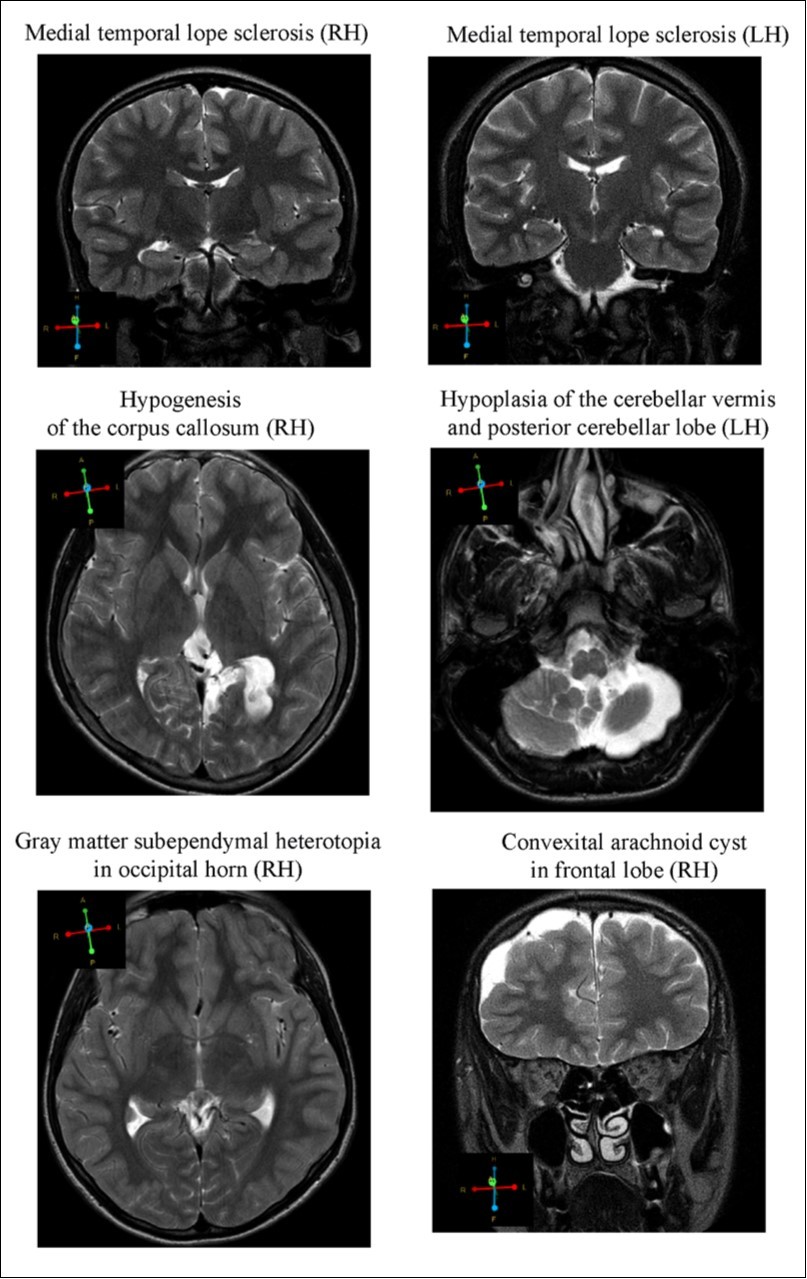

MRI

MR images revealed alterations in brain tissue only in boys with CD (n = 10), however there was no statistical significance between brain malformation and CD. Cerebral dysgenesis was the most prevalent brain abnormality. CD subjects displayed (Figure 2); 1. Medial temporal lobe sclerosis (hypotrophy of either right or left hippocampus) (n = 2); 2. Hypogenesis of the corpus callosum i.e. the band of white matter connecting the two hemispheres of the brain, failed to develop normally and was thinner than in healthy subjects (n = 1); 3. Gray matter heterotrophy, a type of cortical dysplasia, which results in the mislocation of neurons during neuronal migration (n = 2); 4. Arnold-Chiari malformation type II, characterized by a downward displacement of the cerebellar tonsils (hypoplastic cerebellum) through the foramen magnum (n = 1); 5.Arachnoid cysts in the temporal lobe and frontal convex (n = 2). All but two of the subjects described above had mothers with a history of stress and/or various complications during pregnancy and/or labor. Moreover, subjects with the described brain malformations showed signs of epilepsy and/or ADHD they have been excluded – in CD people. Only one subject, having corpus callosum hypogenesis and gray matter heterotrophy in the parietal lobe, showed mild neurological symptoms, having conduct disorder with intellectual disability

Figure 2.Representative images of the brain abnormalities observed in some children with the tendency of antisocial behavior (AST) by Magnetic Resonance Imaging (MRI). Coronal sections (4 mm thick) were acquired by T2 turpbo spin echo (TSE) multi vane (MV) sequence; Axial sections (6mm thick) - T2 TSE.